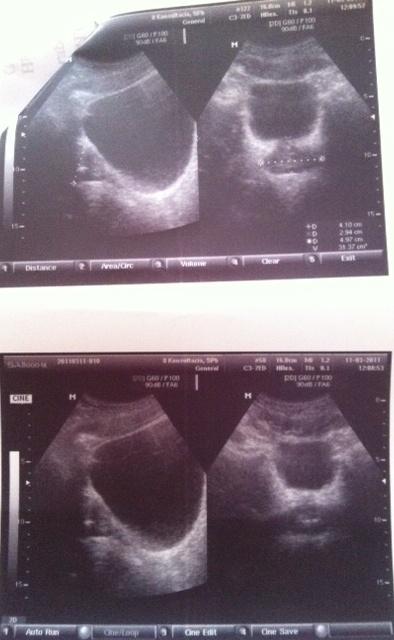

Добрый день! Дайте совет пожалуйста! Мне 30 лет. В декабре 2010 г. обнаружен хронический простатит, сделана узи, назначено лечение :

Псоле второго раза было сделано УЗИ, обнаружено образование камней.